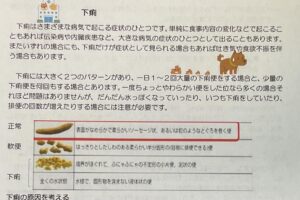

消化器症状は、動物病院に来院する原因としては比較的良くみることができます